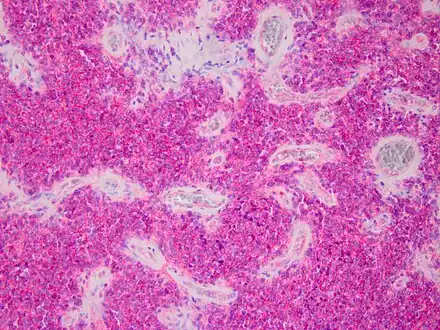

| Micrograph of an H&E stained section of a peripheral PNET. | |